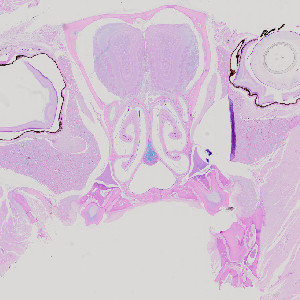

Figure 1

Cross section of rodent head, stained with AB/PAS.